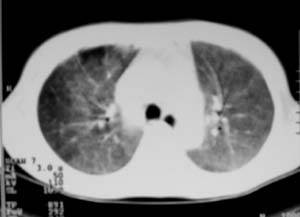

以下是引用zjzjr在2007-9-20 12:29:00的发言:[br]双肺磨玻璃改变,考虑肺水肿.

以下是引用yangzongshan在2007-9-20 18:29:00的发言:[br]两肺毛玻璃样改变,其内可见肺纹理影,无胸腔积液,故考虑肺泡蛋白沉积症

以下是引用276894491在2007-9-20 13:40:00的发言:[br]考虑肺水肿;外源性过敏性肺炎不排除。

以下是引用逸风在2007-9-20 20:45:00的发言:[br]两肺磨玻璃样改变,临床病史短,发热,考虑病毒感染合并右肺代偿性肺气肿.待排肺水肿,病史短,不支持肺泡蛋白沉着症.